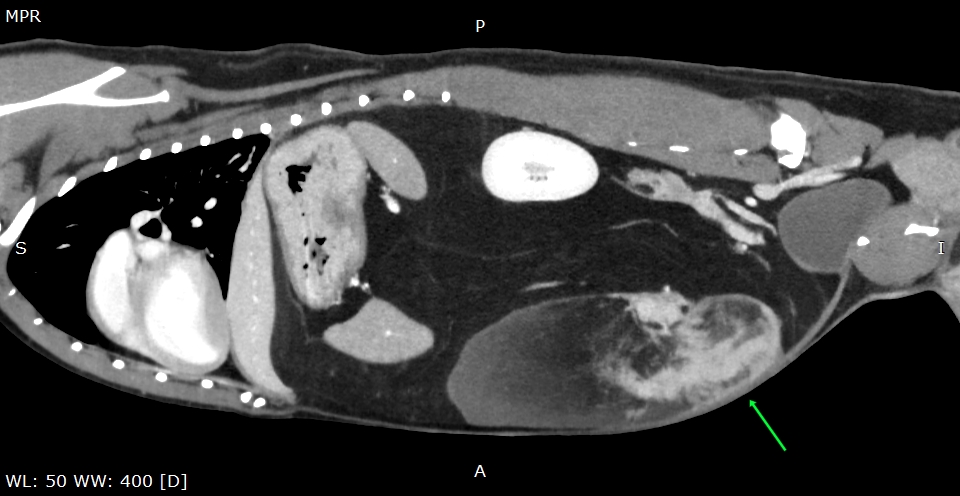

CTでは、大きな脂肪の塊らしきものが複数

特に矢印の白いのが固い脂肪の疑い

その周囲の黒いのが軟らかい脂肪

お腹の中は3/4が脂肪に置き換わっていそうです